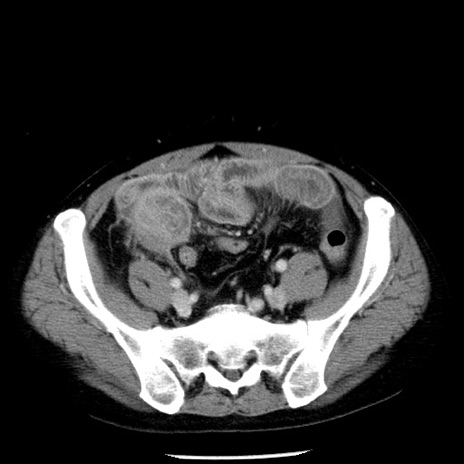

冠状断像

【症例】40歳代男性

【現病歴】2日前から胃痛あり。徐々に周期的な激痛に変化した。本日になっても激痛があるため受診。

【身体所見】意識清明、BT 38-39℃台あり、腹部:膨満、やや硬、右下腹部に圧痛あり。

【データ】WBC 8500、CRP 23.26